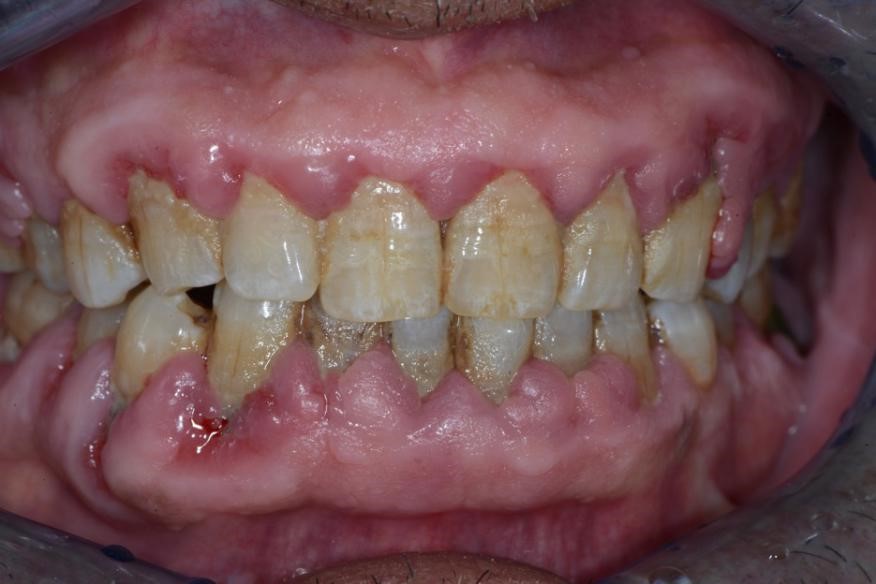

图3:牙周炎治疗前

图4:牙周基础治疗后